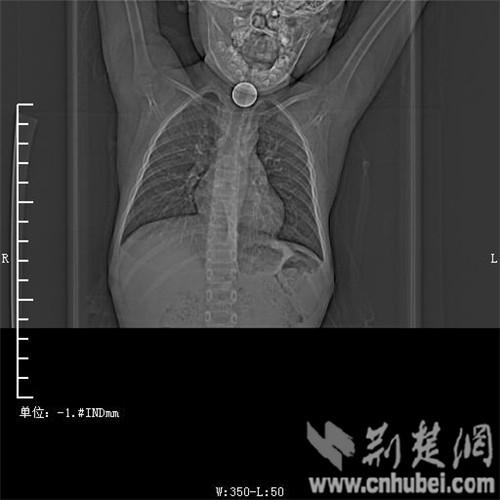

圖為:硬幣卡在了陽陽的喉部

消化內(nèi)主任方向明告訴記者,孩子送來時已經(jīng)是晚上8點15分,醫(yī)護(hù)人員立即給孩子拍胸部CT確定硬幣的位置,8點30分,方向明通過胃鏡下食管異物取出術(shù),成功的將這枚一元硬幣取了出來。1月5日上午,陽陽順利出院,醫(yī)生護(hù)士在他出院時不斷告訴他,以后千萬不要吞含異物。